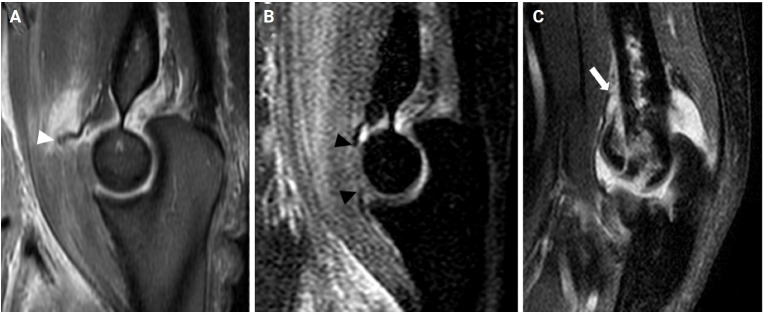

Methods: This study enrolled 21 elbows in DHCS fracture (group A) from 2007 to 2017 and 30 elbows in elbow dislocation (group B) in 2020, all of whom attended a single trauma center. Group A was divided by immobilization period into less than 3 weeks (A1) and more than 3 weeks (A2). Injury patterns of the anterior capsule were divided into proximal stripping, middle displaced, and distal avulsion on magnetic resonance imaging (MRI) scans. Range of motion and functional outcomes were compared between groups A1 and A2.

Results: All patients in group A exhibited proximal stripping of the anterior capsule, while group B showed middle displaced (37%) and distal avulsion (63%) injuries (P<0.001). The mean flexion contracture was 2° in A1 and 8° in A2 (P=0.139), demonstrating no significant difference by immobilization duration. Similarly, the groups had no significant differences in Mayo Elbow Performance Score (MEPS) or Disabilities of the Arm, Shoulder and Hand (DASH) scores.

Conclusions: Flexion contracture following elbow trauma appears to be more closely related to the pattern of anterior capsule injury than the duration of immobilization. Early identification of anterior capsule injury patterns via MRI could inform treatment decisions, particularly in cases where stable surgical fixation is challenging. Prolonged immobilization may be a viable adjuvant treatment option in such cases. Level of evidence: III.